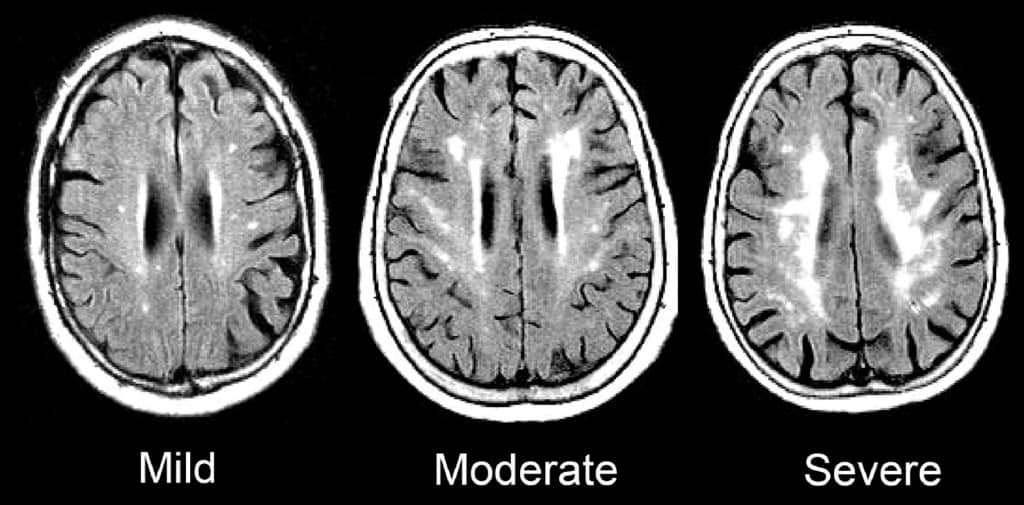

These repeated drops in oxygen, happening night after night, place tremendous stress on the brain, weaken tiny blood vessels, and increase inflammation. Over time, this damage raises the risk of stroke, memory problems, cognitive decline, and even dementia.

Sleep apnea can damage the tiny blood vessels that deliver nutrients to the brain causing microvascular damage.

This same microvascular damage increases the risks of: